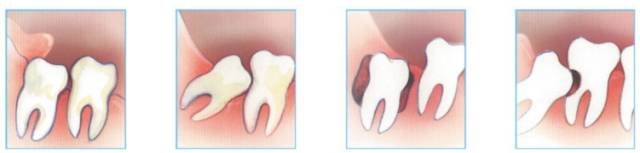

就像人多房子小,开车找车位,是困扰都市人的两大难题,智齿也是一样。因为智齿来得太晚,嘴里的地方已经都被占满了,它往往长不正,由此就带来了一系列的问题。

在口腔临床操作上,对于智齿拔除的适应症,也有很严格的规定,只有在出现以下这些情况时,才会考虑拔除智齿:

龋齿(蛀牙)、造成邻牙病变、 空间不足引起冠周炎症、 局部不易清洁、 无对咬牙、智齿阻生、 引起其他病变、正畸需要、 因阻生疑为不明原因的神经痛病因者,或可疑为病灶牙时,亦应拔除。